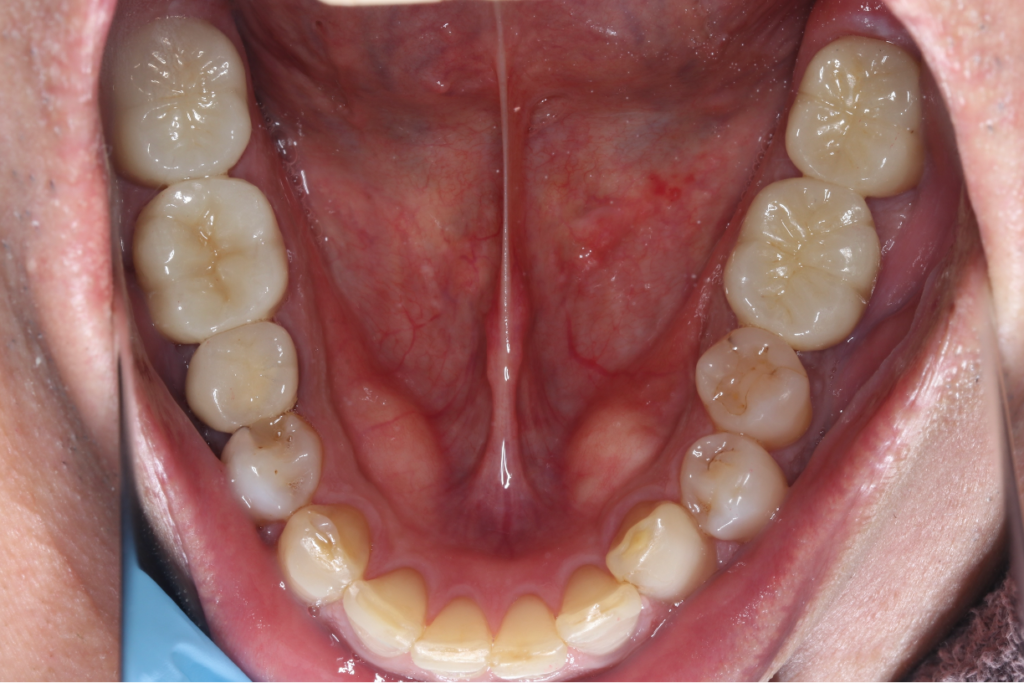

インプラント症例③

年齢 50代女性

治療期間 4ヶ月

インプラントメーカ ストローマンインプラント

治療内容 カスタムアバットメント、上部ジルコニア

治療箇所 左下5番、6番 右下6番、7番

治療費用 1,600,000円